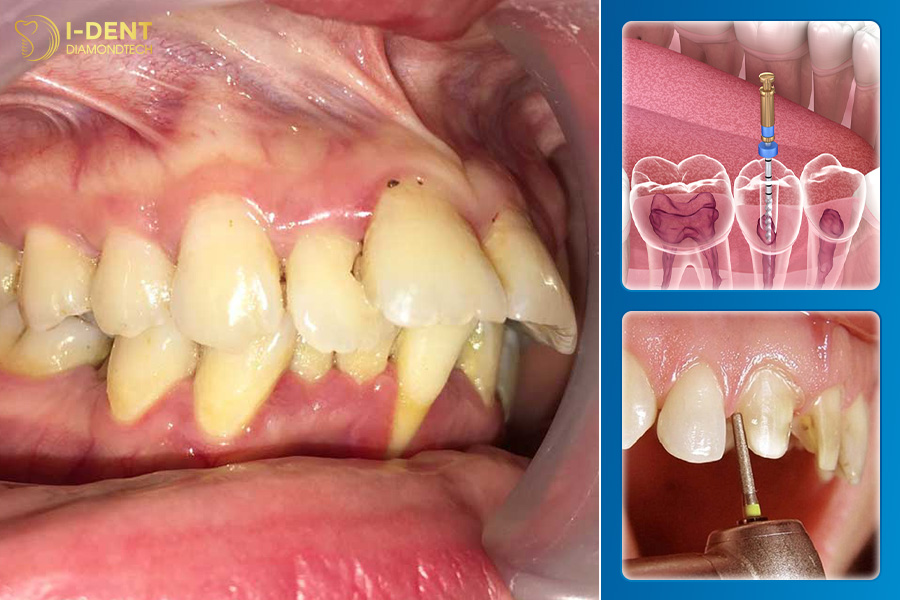

2.2. Bọc răng sứ lấy tủy răng khi răng bị hô, lệch lạc nặng

Răng hô hoặc lệch lạc nặng gây khó khăn trong việc bọc sứ do độ nghiêng của răng quá lớn. Việc mài răng bọc sứ ở những răng này có nguy cơ cao xâm phạm đến buồng tủy nên để ngăn chặn các biến chứng tiềm ẩn như viêm nhiễm tủy, bác sĩ sẽ tiến hành lấy tủy răng trước khi bọc sứ.

Quy trình điều trị tủy răng.